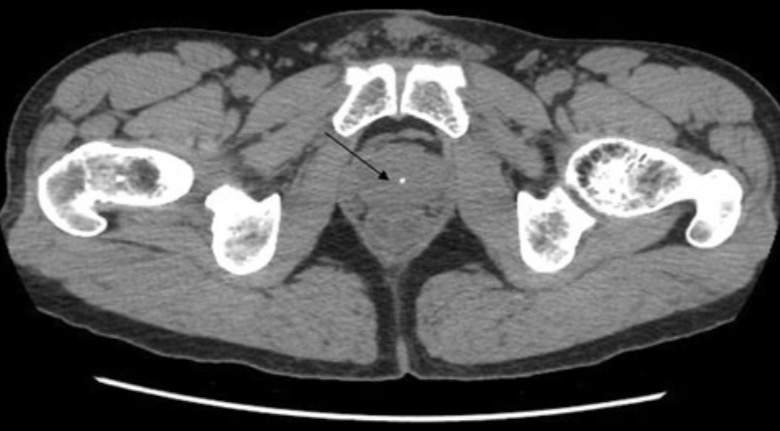

Компьютерная томография таза, демонстрирующая иглу, введенную спереди от ануса и сзади от корня полового члена